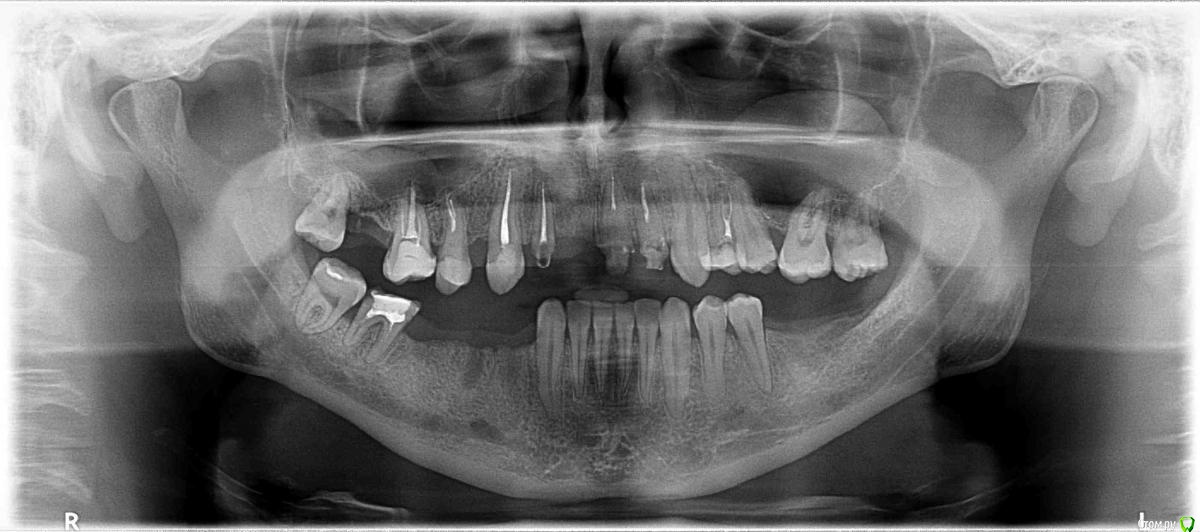

Посоветуйте, пожалуйста, что можно сделать с нижней челюстью, по количеству имплантов. Завтра вечером будут устанавливать, засомневался о количестве имплантов.

Сейчас предлагают установить с левой стороны один имплант на место шестерки, с правой стороны  поставить 2 или еще удалить семерку и поставить еще один (то есть всего 3).  Я так понимаю,  в первом варианте поставить  вместо 4 зубов  3 импланта и мост, или  во втором,  пока оставить семерку, установить на место четверки и шестерки импланты и поставить мост. Есть ли смысл ставить мост или же лучше поставить 4 имланта на отдельных коронках? Снимкам 4 года, нижняя челюсть без изменений, если нужно есть свежие снимки пикассо.